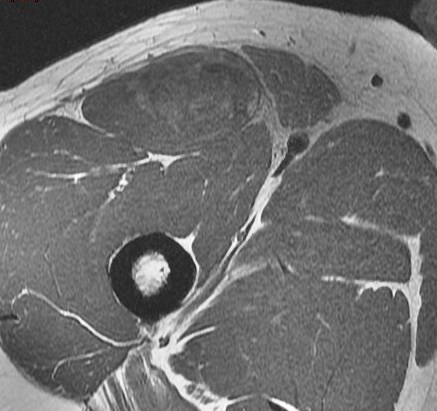

25 y/o work injury, soccer injury.

Maybe his soccer playing is his work? Who am I to ask questions. The indirect head goes on to form the central tendon. There is complete failure of the proximal myotendinous junction and there is an interposed acute hematoma. The hematoma is almost isointense to muscle. Reference article.

rectus femoris indirect head proximal myotendinous junction tear with hematoma( RID2698 )